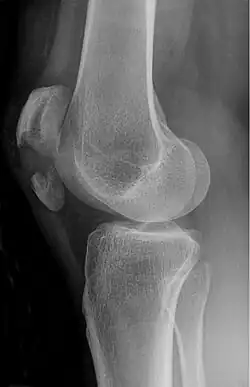

A vertical patella fracture with the fracture line marked by a black arrow

Diagnosis is based on symptoms and confirmed with X-rays.[3] In children an MRI may be required.[3]